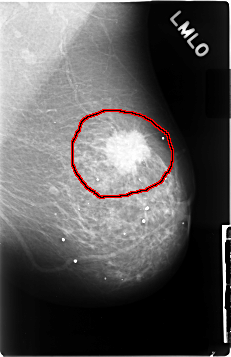

C_0028_1.LEFT_MLO

LEFT_MLO LINES 4632 PIXELS_PER_LINE 3000 BITS_PER_PIXEL 12 RESOLUTION 50 OVERLAY

FILE: C_0028_1.LEFT_MLO.OVERLAY

TOTAL_ABNORMALITIES 1

ABNORMALITY 1

LESION_TYPE MASS SHAPE IRREGULAR MARGINS SPICULATED

ASSESSMENT 5

SUBTLETY 5

PATHOLOGY MALIGNANT

TOTAL_OUTLINES 1

BOUNDARY